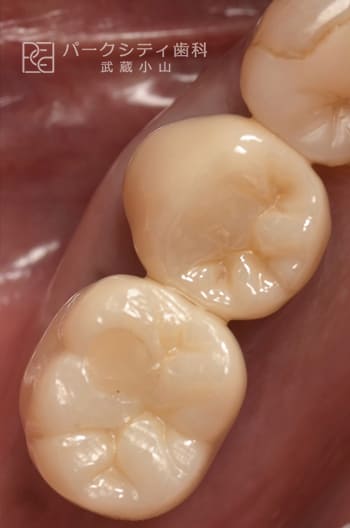

CASE.01

臼歯部を抜歯即時でインプラント治療したケース

- 主訴

- 噛めない

- 治療法

- インプラント治療

- 治療期間

- 4ヶ月

- 費用

- IP:¥275,000

増骨:¥33,000

アバットメント:¥77,000

ジルコニアクラウン:¥99,000

【リスク・副作用】

抜歯直後にインプラントを埋入するため、固定をうまくとることができない場合、また感染をおこしてしまった場合、インプラントと骨が結合しない場合があります。その場合は再手術が必要になります。